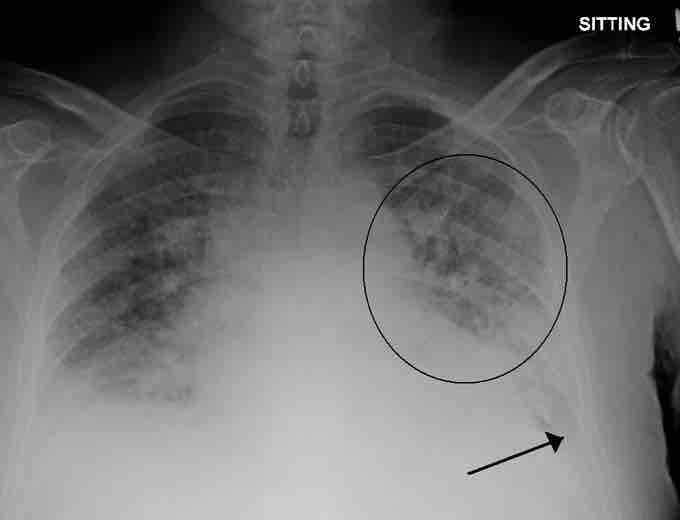

A physiological shunt can develop if there is infection or edema in the lung that obstructs an area. This will decrease ventilation but not affect perfusion; therefore, the V/Q ratio changes and gas exchange is affected .

Pulmonary edema

A physiological shunt can develop if there is infection or edema in the lung which decreases ventilation, but does not affect perfusion; thus, the ventilation/perfusion ratio is affected. Pulmonary edema with small pleural effusions on both sides (as shown) can cause changes in the V/Q ratio.